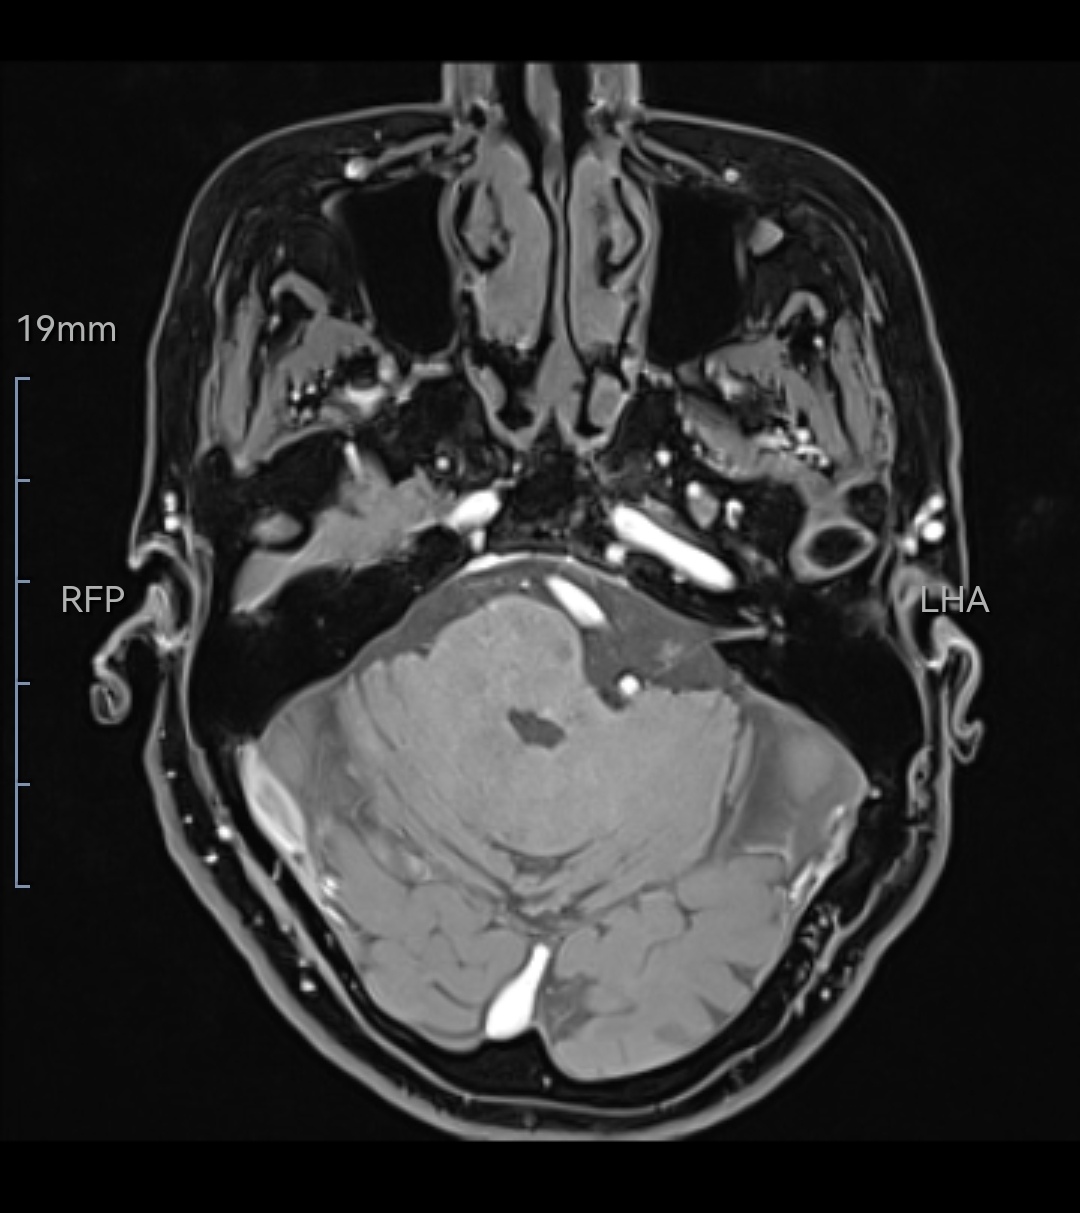

现病史:71岁女性,左侧咽后壁针刺样疼痛10余年,喝水吃饭吞咽动作可以诱发疼痛。近2月疼痛加重,不能忍受。服卡马西平出现头晕手脚麻木。

既往史:8年前在外院诊断为左侧舌咽神经痛,2016年外院行微血管减压术,术后疼痛缓解4年后复发。复发后做过射频消融术、局部阻滞,均无效。

诊断:左侧舌咽神经痛(术后复发)